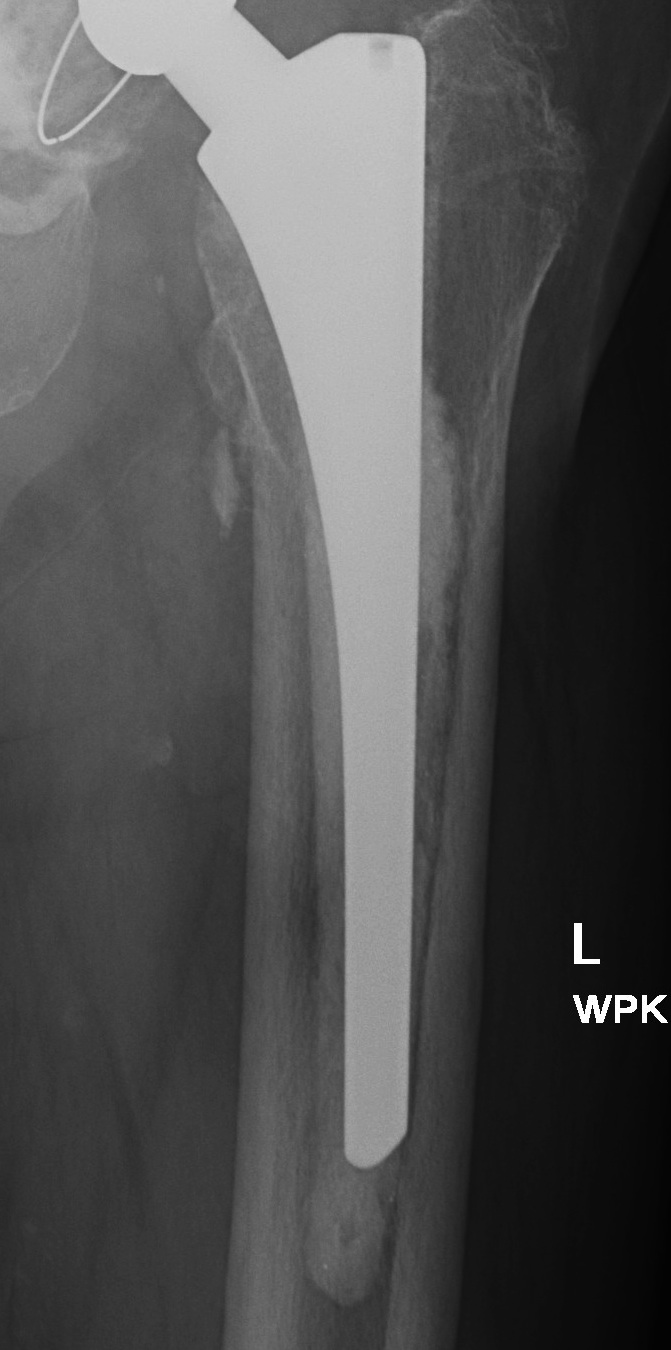

Barrack's femoral component cementation quality grading system

| Grade | Definition |

|---|---|

| A | Complete filling of the medullary canal, without radiolucent lines between the cement and the bone (white-out) |

| B | Radiolucent line covering up to 50% of the cement-bone interface |

| C | Radiolucent line covering between 50% and 99% of the cement-bone interface or incomplete cement mantle |

| D | Complete radiolucent line (100%) at the cement-bone interface and/or absence of cement distally to the end of the stem |

Grade A Grade B Grade C Grade D